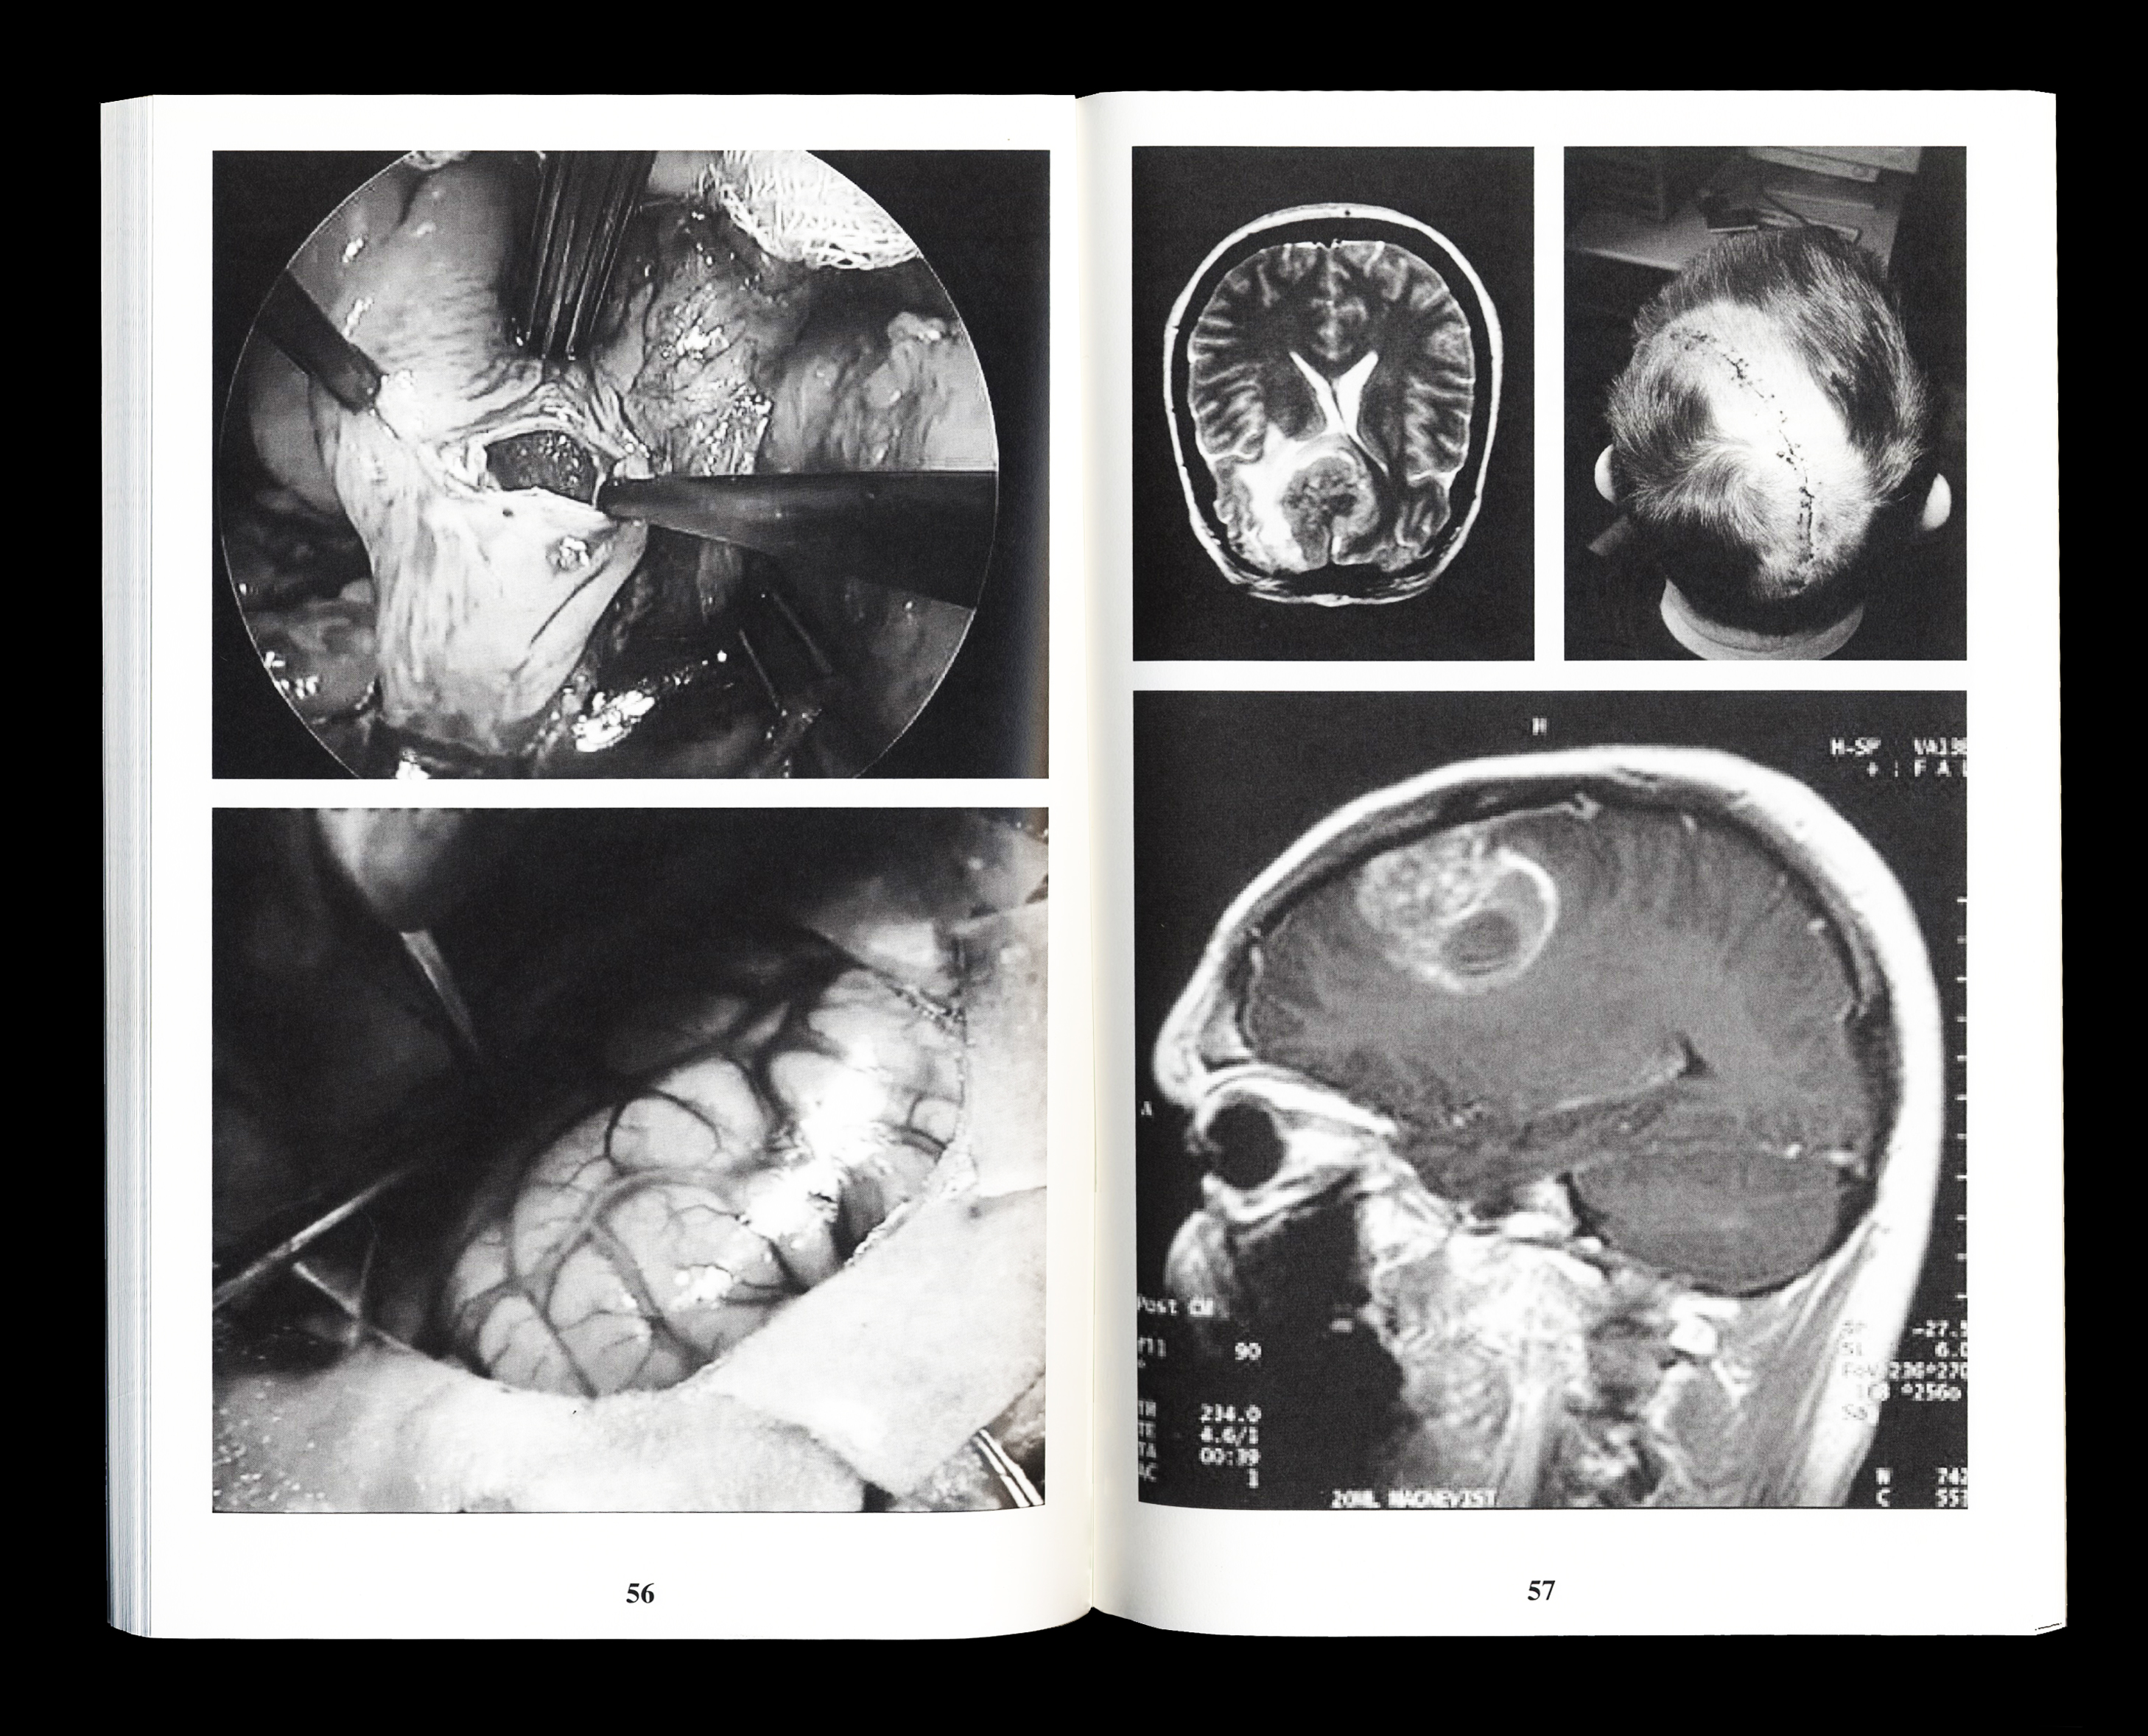

Book about hypochondria on the internet and

the role of Google as your online doctor. If you

have a bit of hypochondria you will read only

the negative results on google about your health

concerns, therefore all the positive words are

erased in the text.